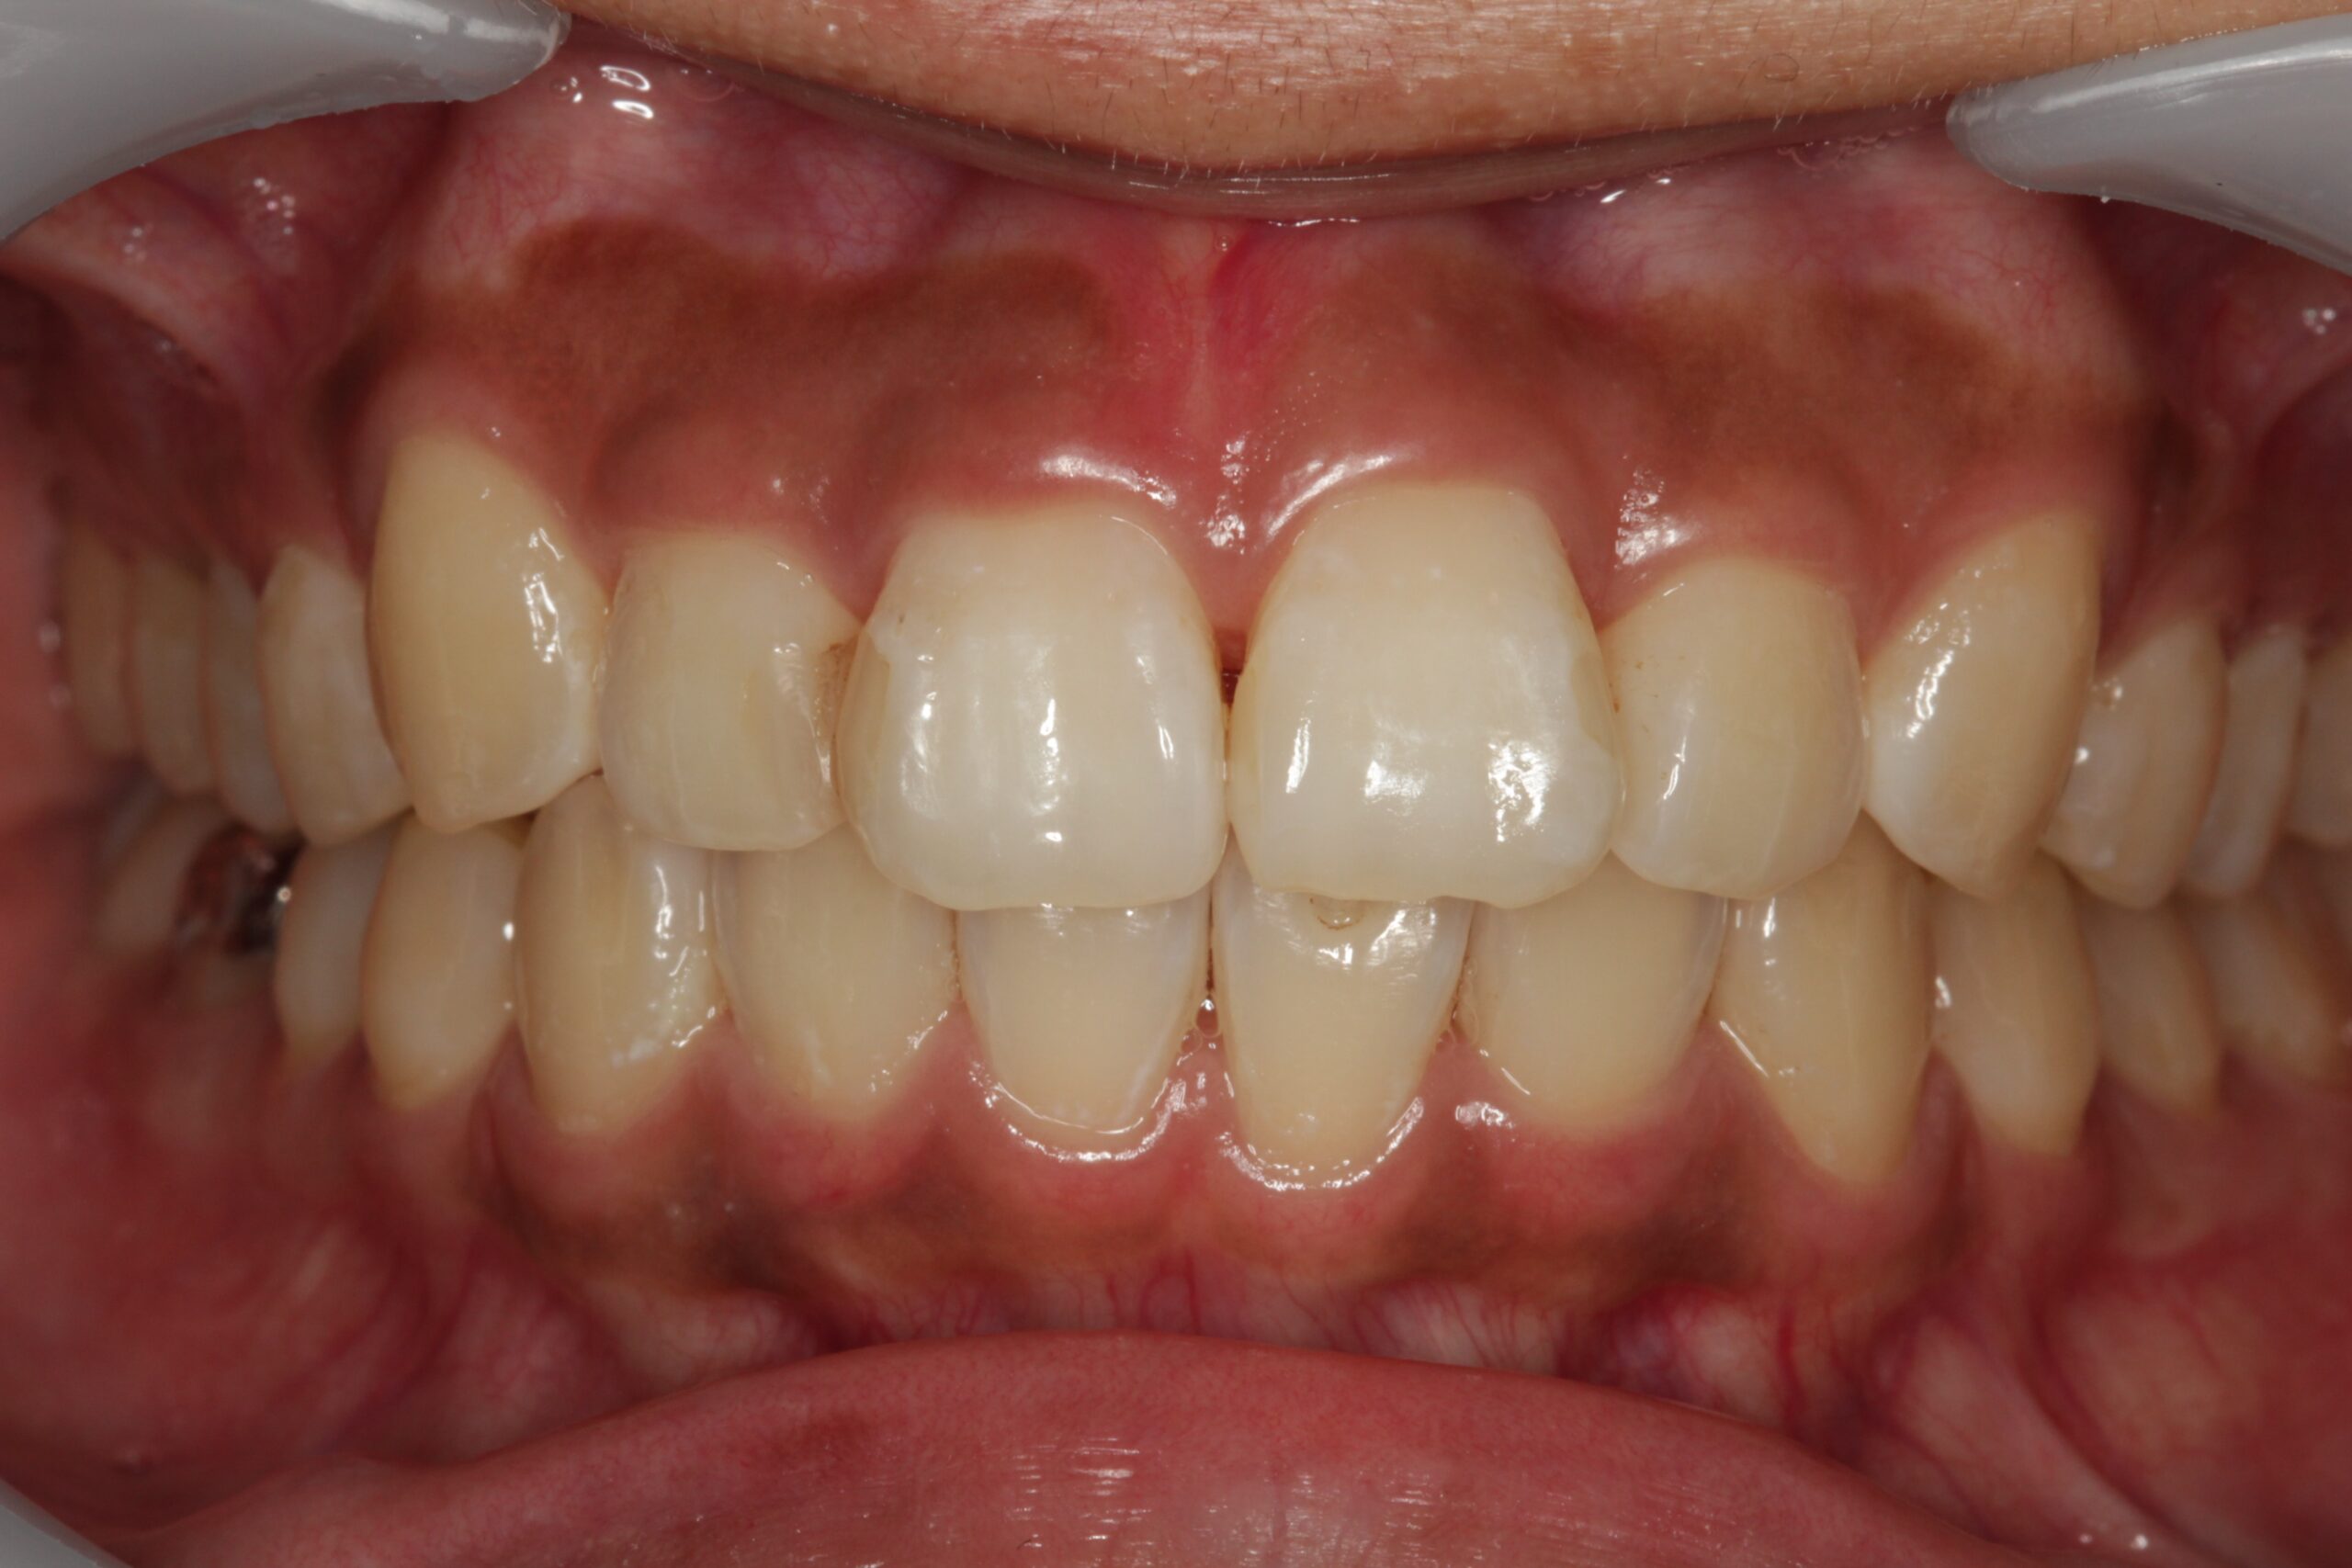

上の前歯が他の歯に比べて前に突き出ている状態です。

見た目のお悩みに限らず、口が閉じにくいためお口の中が乾燥して菌が繁殖し、むし歯や歯周病のリスクが高まります。